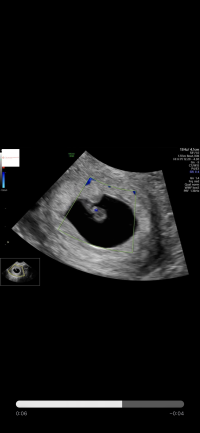

gleder meg iallefall til å se en liten prikk på en skjerm

(forhåpentligvis!)

Han estimerte til 5+6 ved måling

jaja... blir kanskje en bedre opplevelse og verdt å vente til 7+4